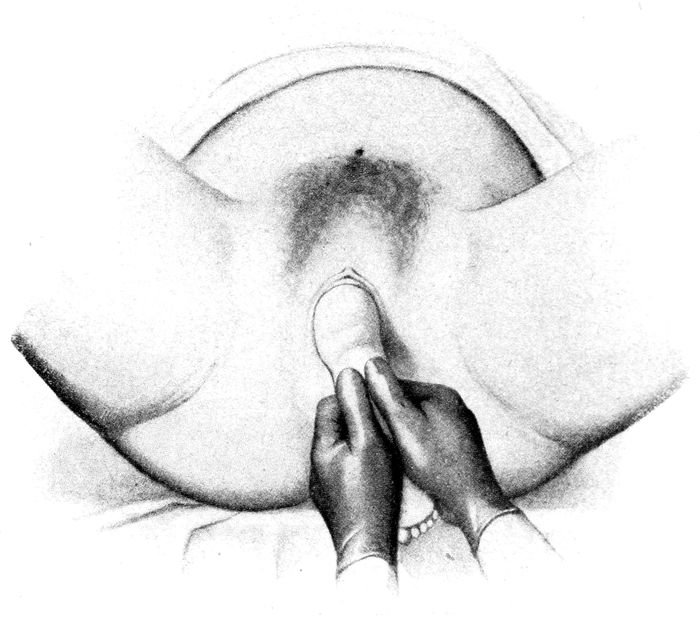

The head passing over the perineum |

117 |